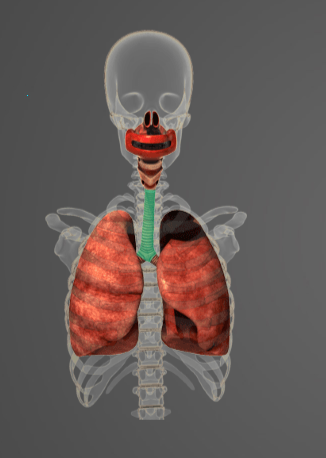

Chystáte se na medicínu nebo vás prostě baví anatomie člověka? Vyzkoušejte si náš poměrně jednoduchý kvíz a uvidíte, jak jste na tom! Hodně štěstí.

-

Question of